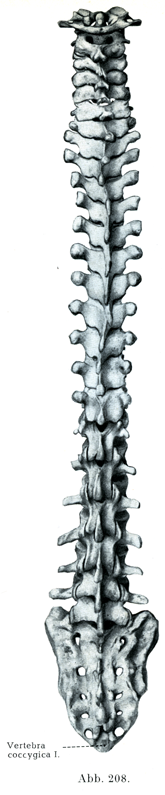

脊柱を後方からみると(図208),各棘突起は概して正中線上に並んでいるが,それは1つ2つの脊椎が偶発的に列を乱している場合や,脊椎群が全体として一定の様式に従って正中線からそれている場合をまず除外してのはなしである.棘突起によって,尖ったひとつづきの高まり(Grat)ができるので,脊柱のことをドイツ語でまたRückgrat(背中の稜)というのである.ところで,この高まりの両側にはWirbelfurchen(脊柱溝)という溝があり,この溝は底は各椎弓の閉鎖部からなり,外側からは,脊柱の頚部および胸部では横突起によって,また腰部では乳頭突起と副突起によってしきられている.項部ではこの溝は広くて浅いが,さらに下方では深く狭くなり,最も狭いところは第12胸椎のところである.これら2本の長い溝に沿って目を走らせれば,横走する椎間隙Zwischenwirbelspaltenが上下に列をなして並んでいる,その全体を見ることができる.この間隙は軟組織のついた骨格では[椎]弓間靱帯Ligamenta interarcualiaという弾性に富む靱帯でいる.椎間隙が最も大きいのは環椎と後頭骨との間で,次に大きいのは環椎と軸椎の間,3番目に大きいのが第5腰椎と仙骨との間である.そのほかの所では,椎間隙は頚部および上胸部ではほんの狭い幅のものであり,胸部脊柱の下1/3から大きくなり,腰椎に至ってさらに大きさを増す.椎間隙の最期のものは仙骨管裂孔にあらわれている.

[図208~210]脊柱 第1尾椎まで(1/4) 図208は後方から,図209は左方から,図210は前方からみたところ.(自然の間隔と自然の弯曲とを保って組み立てたH. Virchowの標本)